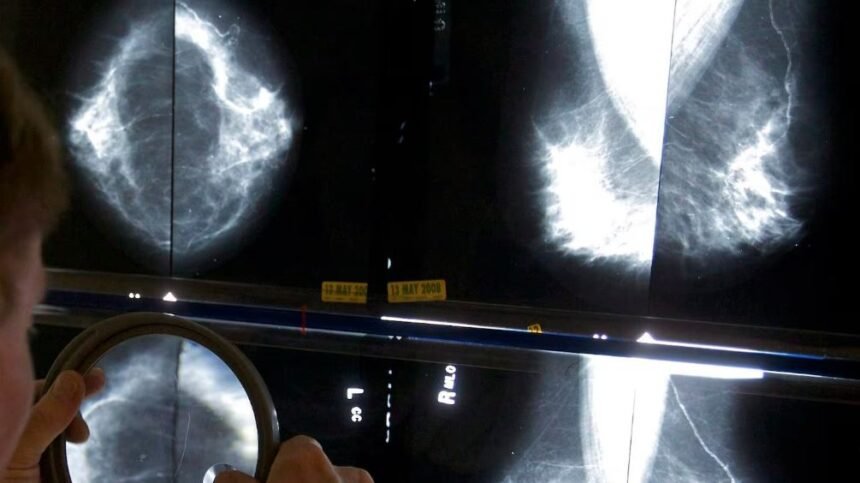

هلا كندا – أظهرت دراسة كندية جديدة وجود فجوة مقلقة في وفيات سرطان الثدي بين النساء ذوي البشرة السمراء والبيض.

وسجلت النساء السود من أصول كاريبية معدلات وفاة أعلى بنسبة تصل إلى 70% في الفئة العمرية الممتدة بين 40 و49 عامًا، وبنسبة 42% بين 50 و59 عامًا.

وقالت الدراسة إن النساء ذوي البشرة السمراء يُصبن بالمرض في سن أصغر، إذ يتراوح متوسط عمر الوفاة بين 53 و66 عامًا، مقابل 71 عامًا لدى النساء البيض.

فيما تُشخّص أكثر من نصف الحالات بين النساء ذوي البشرة السمراء قبل سن الخمسين، مقارنة بـ14% فقط لدى النساء البيض.

وذكرت الطبيبة آنا ويلكنسون أن سرطان الثدي «ليس مرضًا واحدًا»، وأن أنماطه البيولوجية تختلف بين المجموعات، مؤكدة أن النساء ذوي البشرة السمراء أكثر عرضة للإصابة بأنواع عدوانية مثل «الثلاثي السلبي»، الذي يظهر لديهن بنسبة تصل إلى 21% مقابل 9.9% لدى النساء البيض.

وأشارت الدراسة أيضًا إلى أن النساء ذوي البشرة السمراء يُشخّصن بمراحل متقدمة، إذ اكتُشفت 39% من الحالات في المرحلة الأولى لديهن، مقابل 50% لدى النساء البيض.

ودعت الطبيبة عائشة لوفتيرز إلى اعتماد نموذج فحص قائم على تقييم المخاطر الفردية، يشمل عوامل مثل العمر والأنماط الجينية والخلفية العرقية، بدلًا من الاعتماد فقط على العمر. وأكدت أن البيانات الحالية «تنبه إلى فجوات واضحة» تستدعي تغييرًا في استراتيجية الفحص.

ويطالب خبراء وجماعات دعم مرضى السرطان بإنشاء إرشادات وطنية موحدة تُعرّف مستويات المخاطر وتحدد طرق الفحص وعدد مرات التصوير المناسبة لكل فئة، لضمان عدالة الخدمات بين جميع المقاطعات.

وأكدت الشبكة الكندية لسرطان الثدي أن النموذج الحالي «يُفوّت الكثير من الحالات» لأنه يعتمد على عامل واحد هو العمر.

في وقت تتزايد فيه الإصابات بين الشابات وتبرز فيه اختلافات واضحة بين المجموعات السكانية.

وتشير الدراسة إلى أن مواجهة الظاهرة تتطلب أيضًا تحسين إمكانية الوصول إلى خدمات الرعاية، ومعالجة النقص في الأطباء، وتجديد آليات التعامل مع شكاوى النساء الأصغر سنًا، اللواتي تُهمل أعراضهن في بعض الحالات، ما يؤدي إلى التشخيص المتأخر.